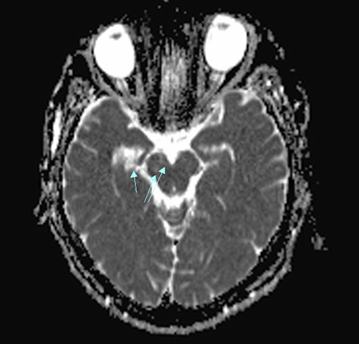

Figure 4 The localization of injuries in Parinau's syndrome.

Notes: A - scheme of the midbrain, B – MRI of lesions, 1 - dorsal midbrain syndrome, 2 - ventral midbrain syndrome, arrow – locals of the neurodegeneration.